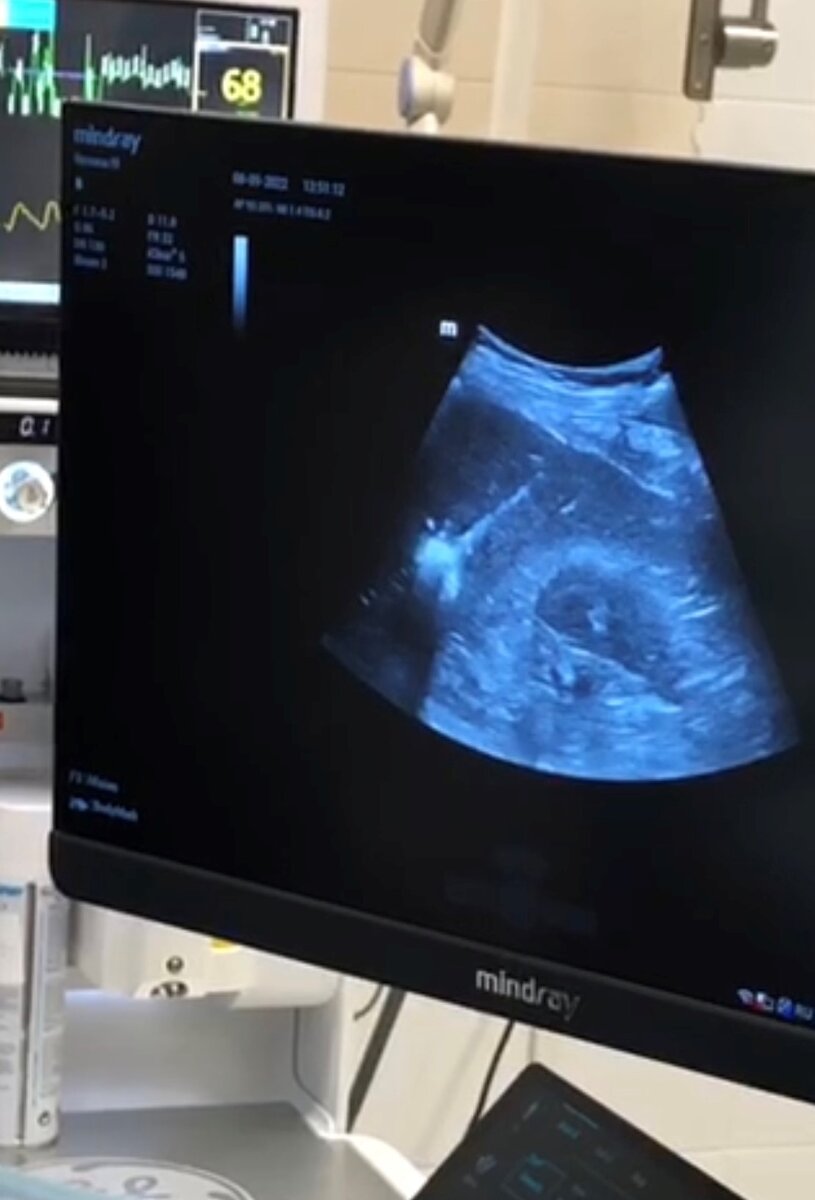

На экране УЗИ-аппарата запечатлен процесс разрушения метастаза в печени во время МВА

- непосредственное воздействие микроволн на опухоль, полнота разрушения очага оценивается по УЗИ в режиме реального времени (время воздействия от 2 до 20 минут)